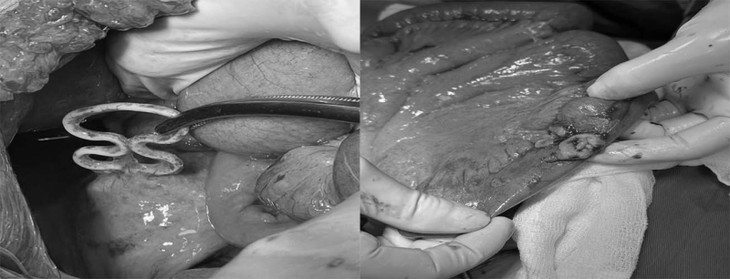

| Dụng cụ tử cung lạc chỗ đâm xuyên tử cung, thủng ruột non. Ảnh BVCC |

BSCKII Dương Xuân Hiệp – Trưởng Khoa Ngoại Tổng hợp, BSCKI Tô Thị Kim Quy – Trưởng Khoa Phụ Sản, Bệnh viện Bãi Cháy đã tiến hành phẫu thuật cấp cứu xử trí tổn thương cho người bệnh. Quá trình phẫu thuật quan sát thấy ổ bụng bẩn có dịch đục, thức ăn, thân tử cung mặt trước có dụng cụ tử cung dạng vòng số 8 (1/3 vòng cắm trong cơ tử cung 2/3 vòng nằm ngoài tử cung), quai ruột non vị trí sát thân tử cung rách ngang kích thước khoảng 2cm, đang thoát dịch tiêu hóa.

Các bác sĩ đã tiến hành lấy dụng cụ tử cung trên cơ tử cung, khâu phục hồi cơ tử cung, lỗ thủng ruột non, cầm máu, lau rửa và đặt dẫn lưu ổ bụng. Sau phẫu thuật 24h, sức khỏe bệnh nhân ổn định và được theo dõi sát quá trình hồi phục.